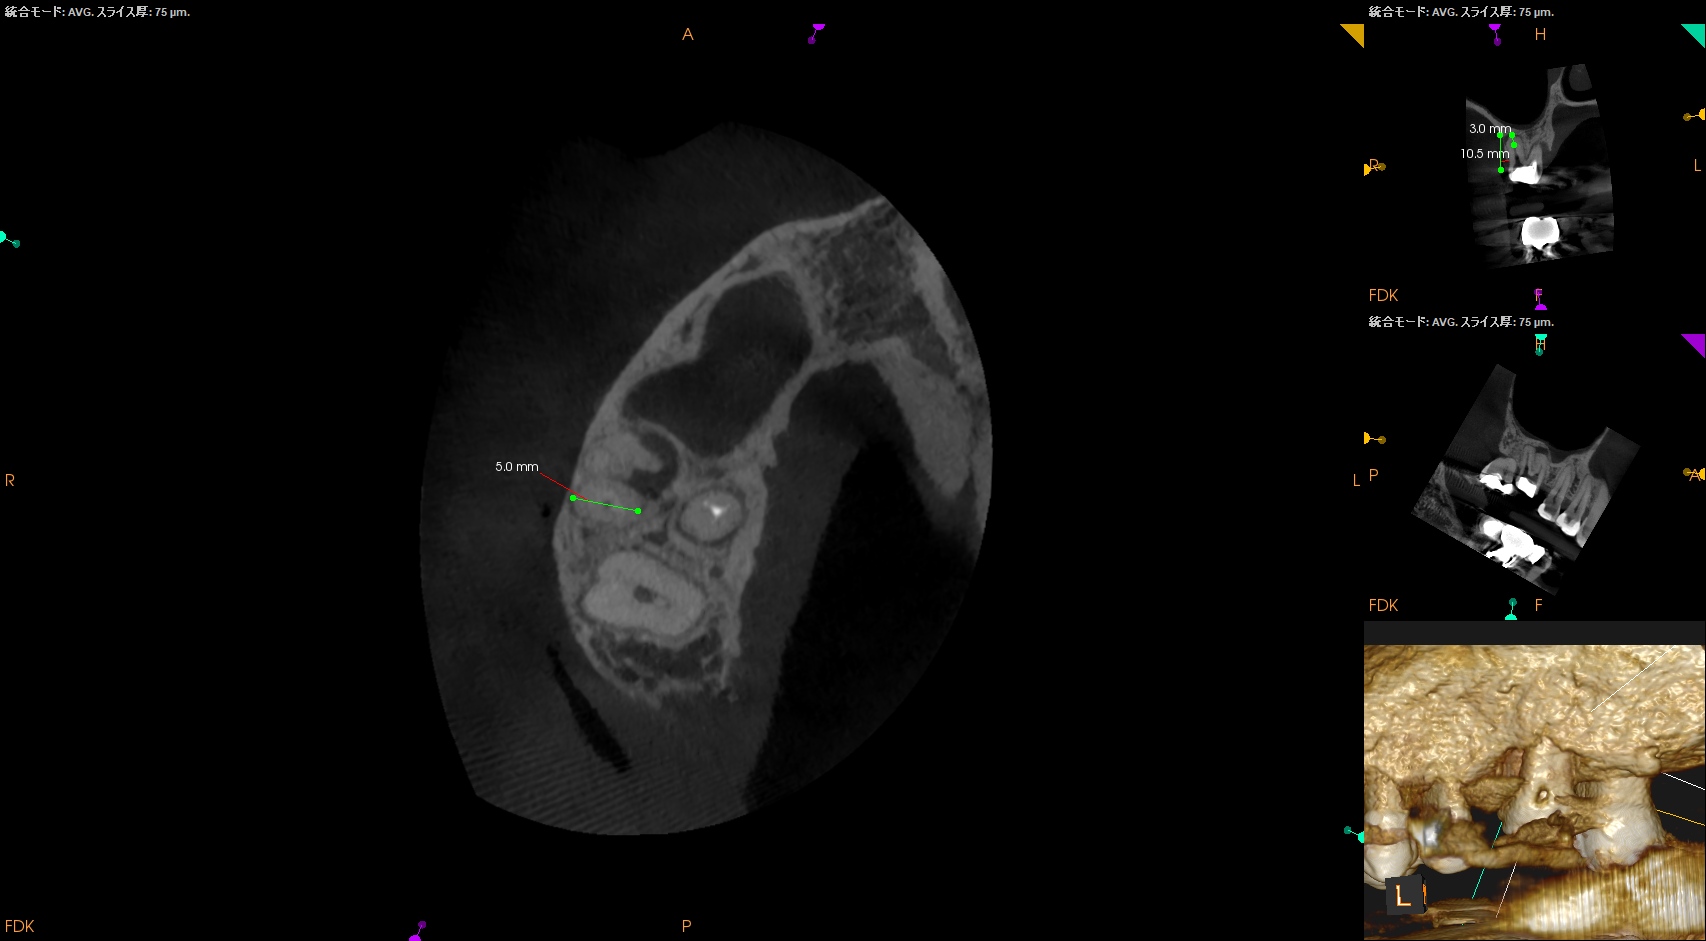

DB

DBはCEJよりも10.5mm下方にApexがあり、そこを3mmで切断するには5mmの頬舌的幅が必要で1根管なことからここはEasyだ。